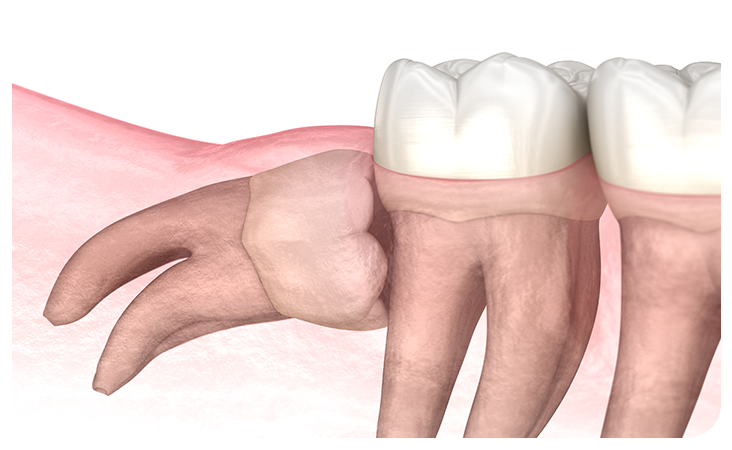

매복사랑니란?

사랑니가 완전히 맹출 되지 않고 잇몸 아래 묻혀있는

형태의 사랑니를  매복 사랑니라고 합니다.

사랑니가 완전히 맹출 되지 않고 잇몸 아래에 묻혀있는 형태의 사랑니를 매복 사랑니라고 합니다.

매복 사랑니는 함치성낭종, 염증 유발, 턱뼈 손상 등의 문제를 유발할 수 있어 발치해주는 것이 좋습니다.

부분매복

수직매복

원심경사 매복

수평매복